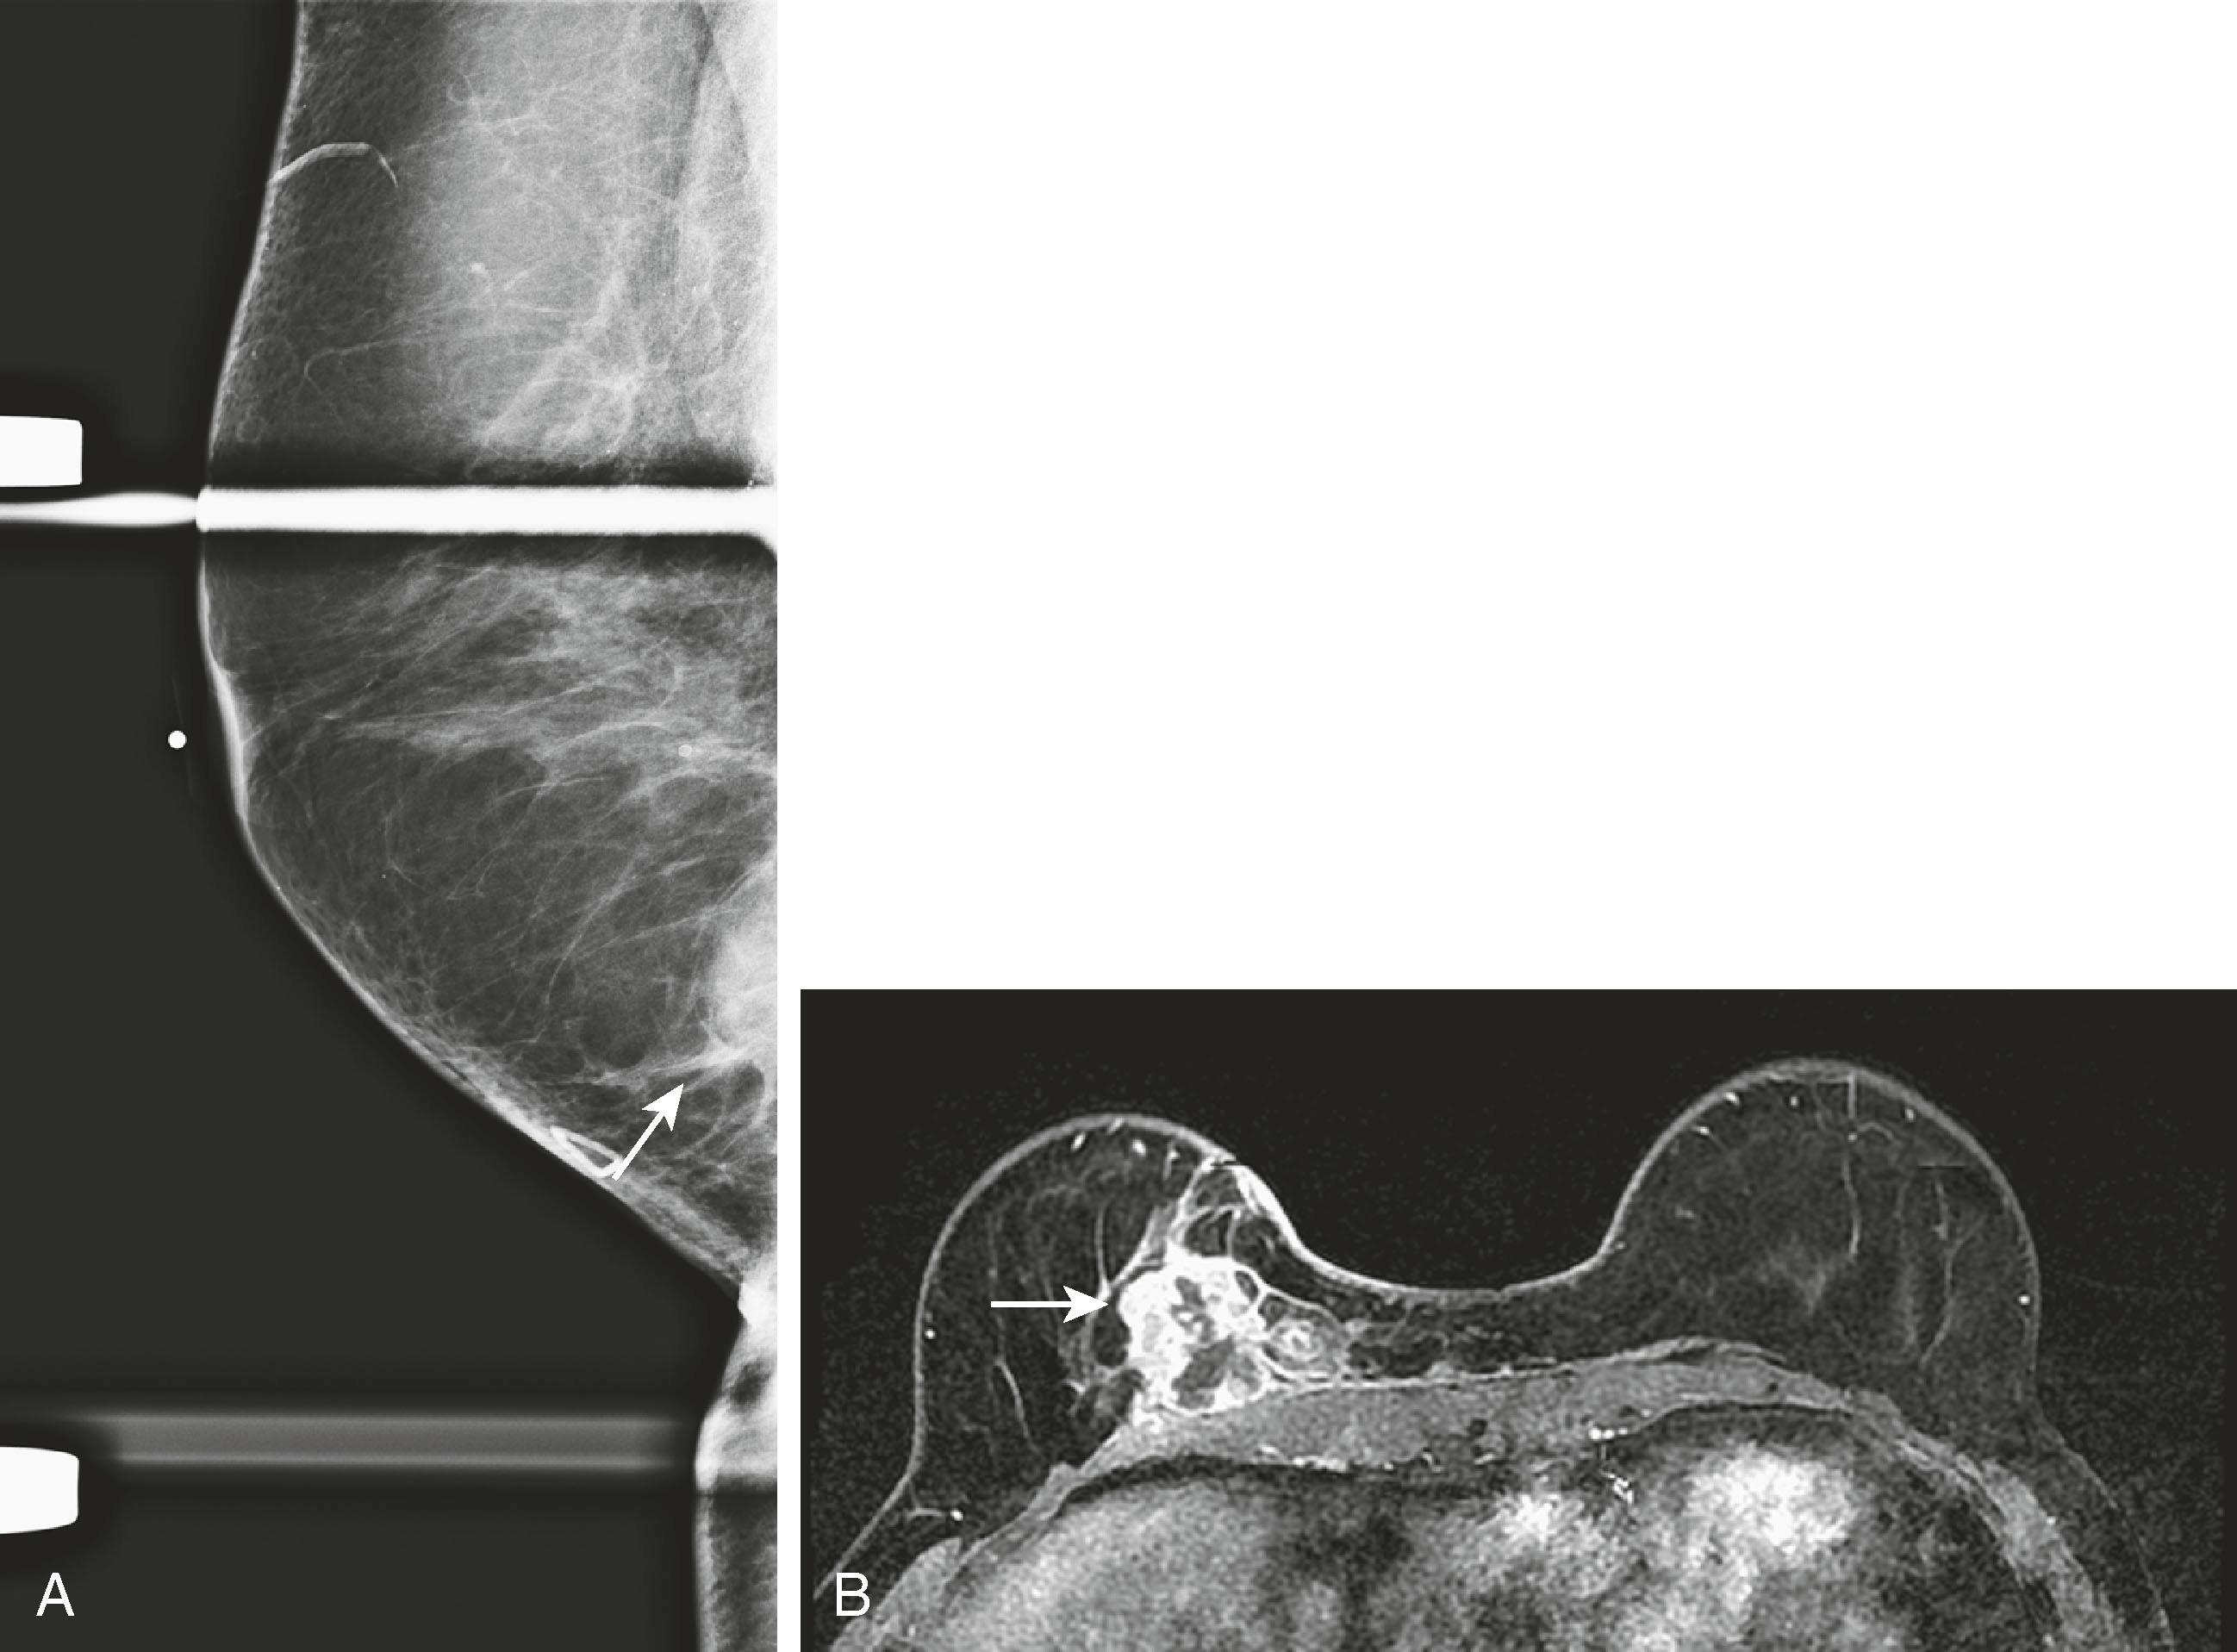

Most still believe that breast MRI is a valuable test for preoperative surgical planning when breast conservation is being considered, and most importantly if pathology reveals lobular carcinoma. It appears to be most helpful in women with dense breast tissue in whom mammography is limited, but there are no generally accepted guidelines for which patients should be evaluated by MRI before surgery. Because of the high sensitivity and lower specificity of breast MRI, it is not infrequent that false-positive lesions are discovered. Fig. 8.30 demonstrates an instance in which MRI demonstrated more extensive tumor than expected.

Fig. 8.30, ( A ) A 57-year-old woman has a palpable mass partially seen on spot compression mediolateral oblique views (arrow) . ( B ) Magnetic resonance imaging shows a much larger tumor (arrow) than originally expected based on the physical examination and mammogram.

Breast MRI has become the gold-standard test to search for a breast primary when a patient presents with a carcinoma of unknown primary. It is valuable not only because of its high sensitivity in identifying the primary tumor but also because of its high negative predictive value. Liberman and associates noted in a small study group of 16 women that MRI identified the primary breast tumor in 13 out of 16 patients. MRI may be of greatest value when a patient presents with axillary lymphadenopathy and a negative mammogram. Fig. 8.35 demonstrates such a patient who presented with axillary lymphadenopathy and a negative mammogram.

Fig. 8.35, A 42-year-old woman was noted to have prominent right axillary lymph nodes and had excisional biopsy of one of the lymph nodes, which revealed carcinoma. Her mammogram did not reveal the primary carcinoma. ( A ) Abnormal mammogram of the right breast. ( B ) Right axillary ultrasound demonstrates enlarged lymph nodes (arrow) . ( C ) Magnetic resonance imaging (MRI) demonstrates the right axillary adenopathy (arrow) . ( D ) MRI additionally demonstrates the occult primary breast malignancy (arrow) .